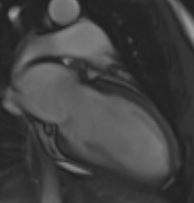

2 Chamber View